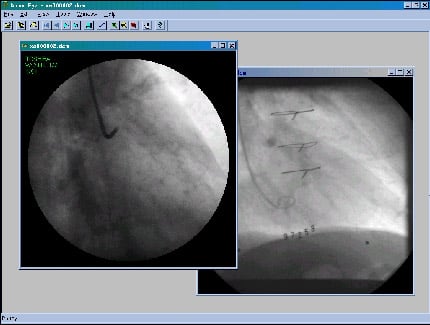

Para consulta das informações contidas nos servidores de imagem, distribuídos na rede de alta velocidade, um conjunto de aplicações para visualização de imagens médicas utilizando o protocolo DICOM foram desenvolvidas. Em especial, os visualizadores implementados apresentam, ainda, a capacidade para análise de estudos contendo imagens dinâmicas, os quais tornam-se possível com a infra-estrutura baseada em rede de banda larga.

A Figura 7 apresenta a interface gráfica e a imagem obtida em um estudo típico de cineangiografia contento cerca de 400 Mbytes de informação.

Figura 7: Interface gráfica do visualizador e imagem típica de cineangiografia.